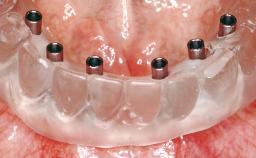

# of Implants 6

Type of Implants One-Piece

Modality 6+ implants with immediate loading

Loading Protocol Immediate